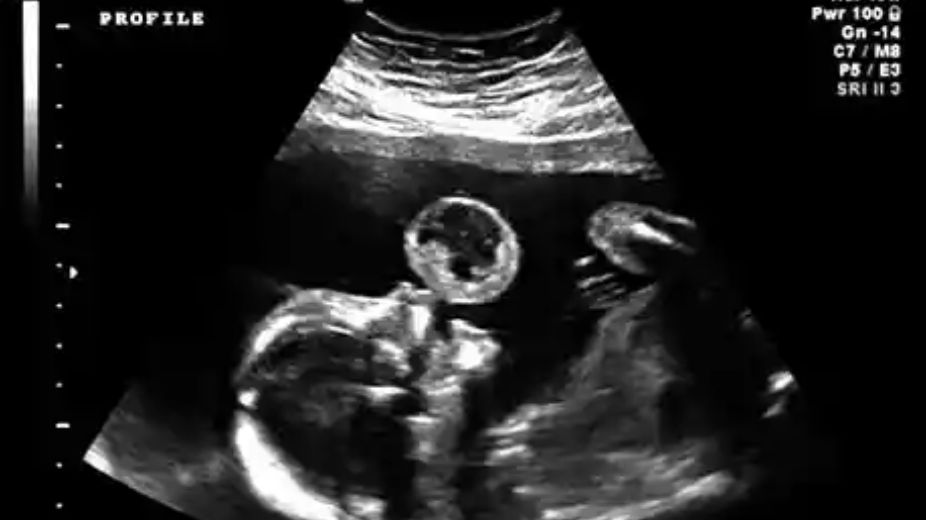

Na jednym z rutynowych badań USG w trakcie ciąży u Tammy Gonzalez lekarz ginekolog zauważył ogromną bańkę. Na pierwszy rzut oka wyglądało to, jakby dziecko wydmuchiwało coś z ust. Okazało się jednak, że jest to potworniak.

Tammy zobaczyła na USG, że tuż obok jej dziecka znajduje się wielka bańka. Wyglądało to tak, jakby to ono puszczało ją z ust. "To jest we mnie czy dziecko to robi?" - zapytała lekarza.

Bańka była jednak czymś znacznie bardziej szkodliwym niż tylko punktem na ekranie. Po dalszych badaniach okazało się, że jest to niezwykle rzadki i śmiertelny nowotwór — potworniak. Zdarza się w 1 przypadku na 100 tys. urodzeń. Rak rósł na ustach dziecka.